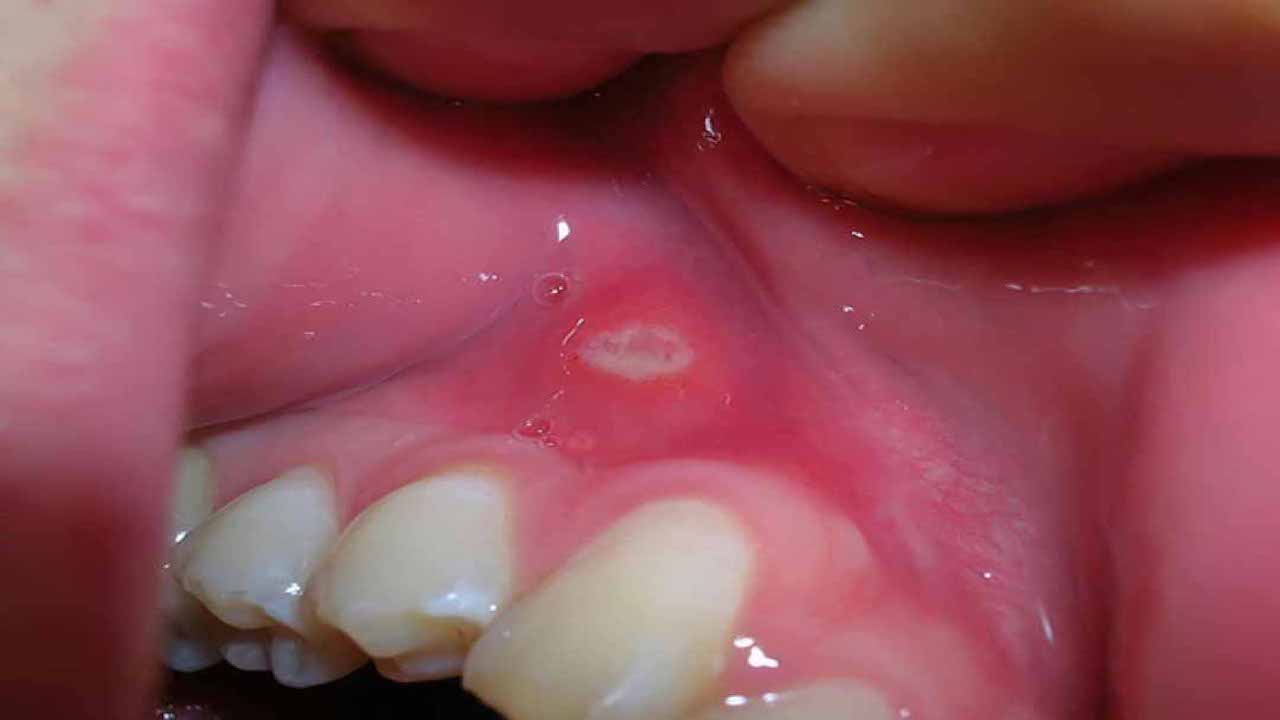

Nhiệt miệng là một bệnh lý phổ biến, biểu hiện bằng sự xuất hiện của các vết loét nhỏ, có màu trắng hoặc vàng, viền đỏ xung quanh. Các vết loét này có thể hình thành trên nướu, môi, má, lưỡi, hoặc dưới lưỡi. Mặc dù không lây lan và thường không ăn sâu vào biểu bì, nhưng chúng gây ra cảm giác đau rát, đặc biệt khi ăn các món chua, cay nóng.